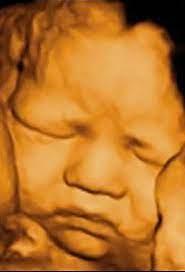

TOP BEST 3D/4D ULTRASOUND IMAGING CENTRE IN SECTOR...